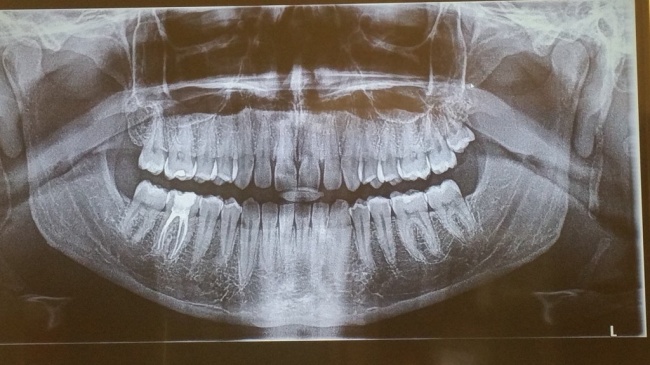

15. Φρονιμίτες

Το 20% των ανθρώπων δεν έχουν φρονιμίτες, κάτι το οποίο θεωρείται φυσιολογικό. Η εμφάνιση τους ποικίλλει μεταξύ των διαφόρων πληθυσμών. Για παράδειγμα, σχεδόν το 100% των αυτόχθονων Μεξικανών δεν έχουν φρονιμίτες, ενώ ουσιαστικά όλοι οι αβορίγινες της Τασμανίας έχουν. Η διαφορά σχετίζεται με το γονίδιο PAX9 (και ίσως και άλλα γονίδια).